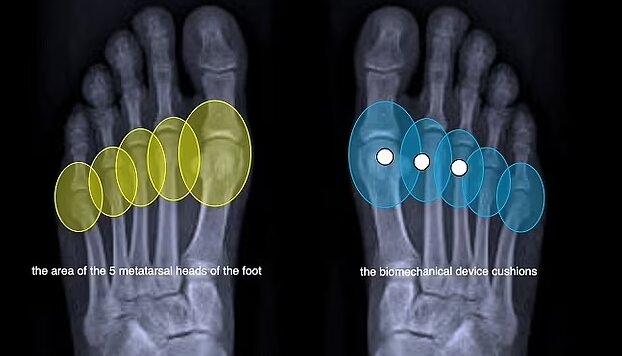

کفشهای پاشنهبلند، تمام وزن کاربر را روی قسمت جلوی پا قرار میدهند و فشار شدیدی را بر انتهای استخوانهای کف پا و مفاصل بین انگشتان و پا وارد میکنند. این امر به افزایش خطر شکستگی استخوان، ضخیم شدن بافت اطراف عصب پا و سایر آسیبهای احتمالی منجر میشود.

این کفی که توسط شرکت ایتالیایی «GAIT-TECH» ساخته شده است، ضربه را هنگام راه رفتن از بین میبرد و فشار را در سراسر پا پخش میکند. این کفی در دید نیست و به طور ناخوشایند زیر پا تکان نمیخورد.

به گفته این شرکت مستقر در کاپری، نوآوری بیومکانیکی این کفی که از پلیمر بازیافتی ساخته شده است، سلامتی زنان را بهبود میبخشد، درد را تسکین میدهد و از بروز آسیبها جلوگیری میکند.